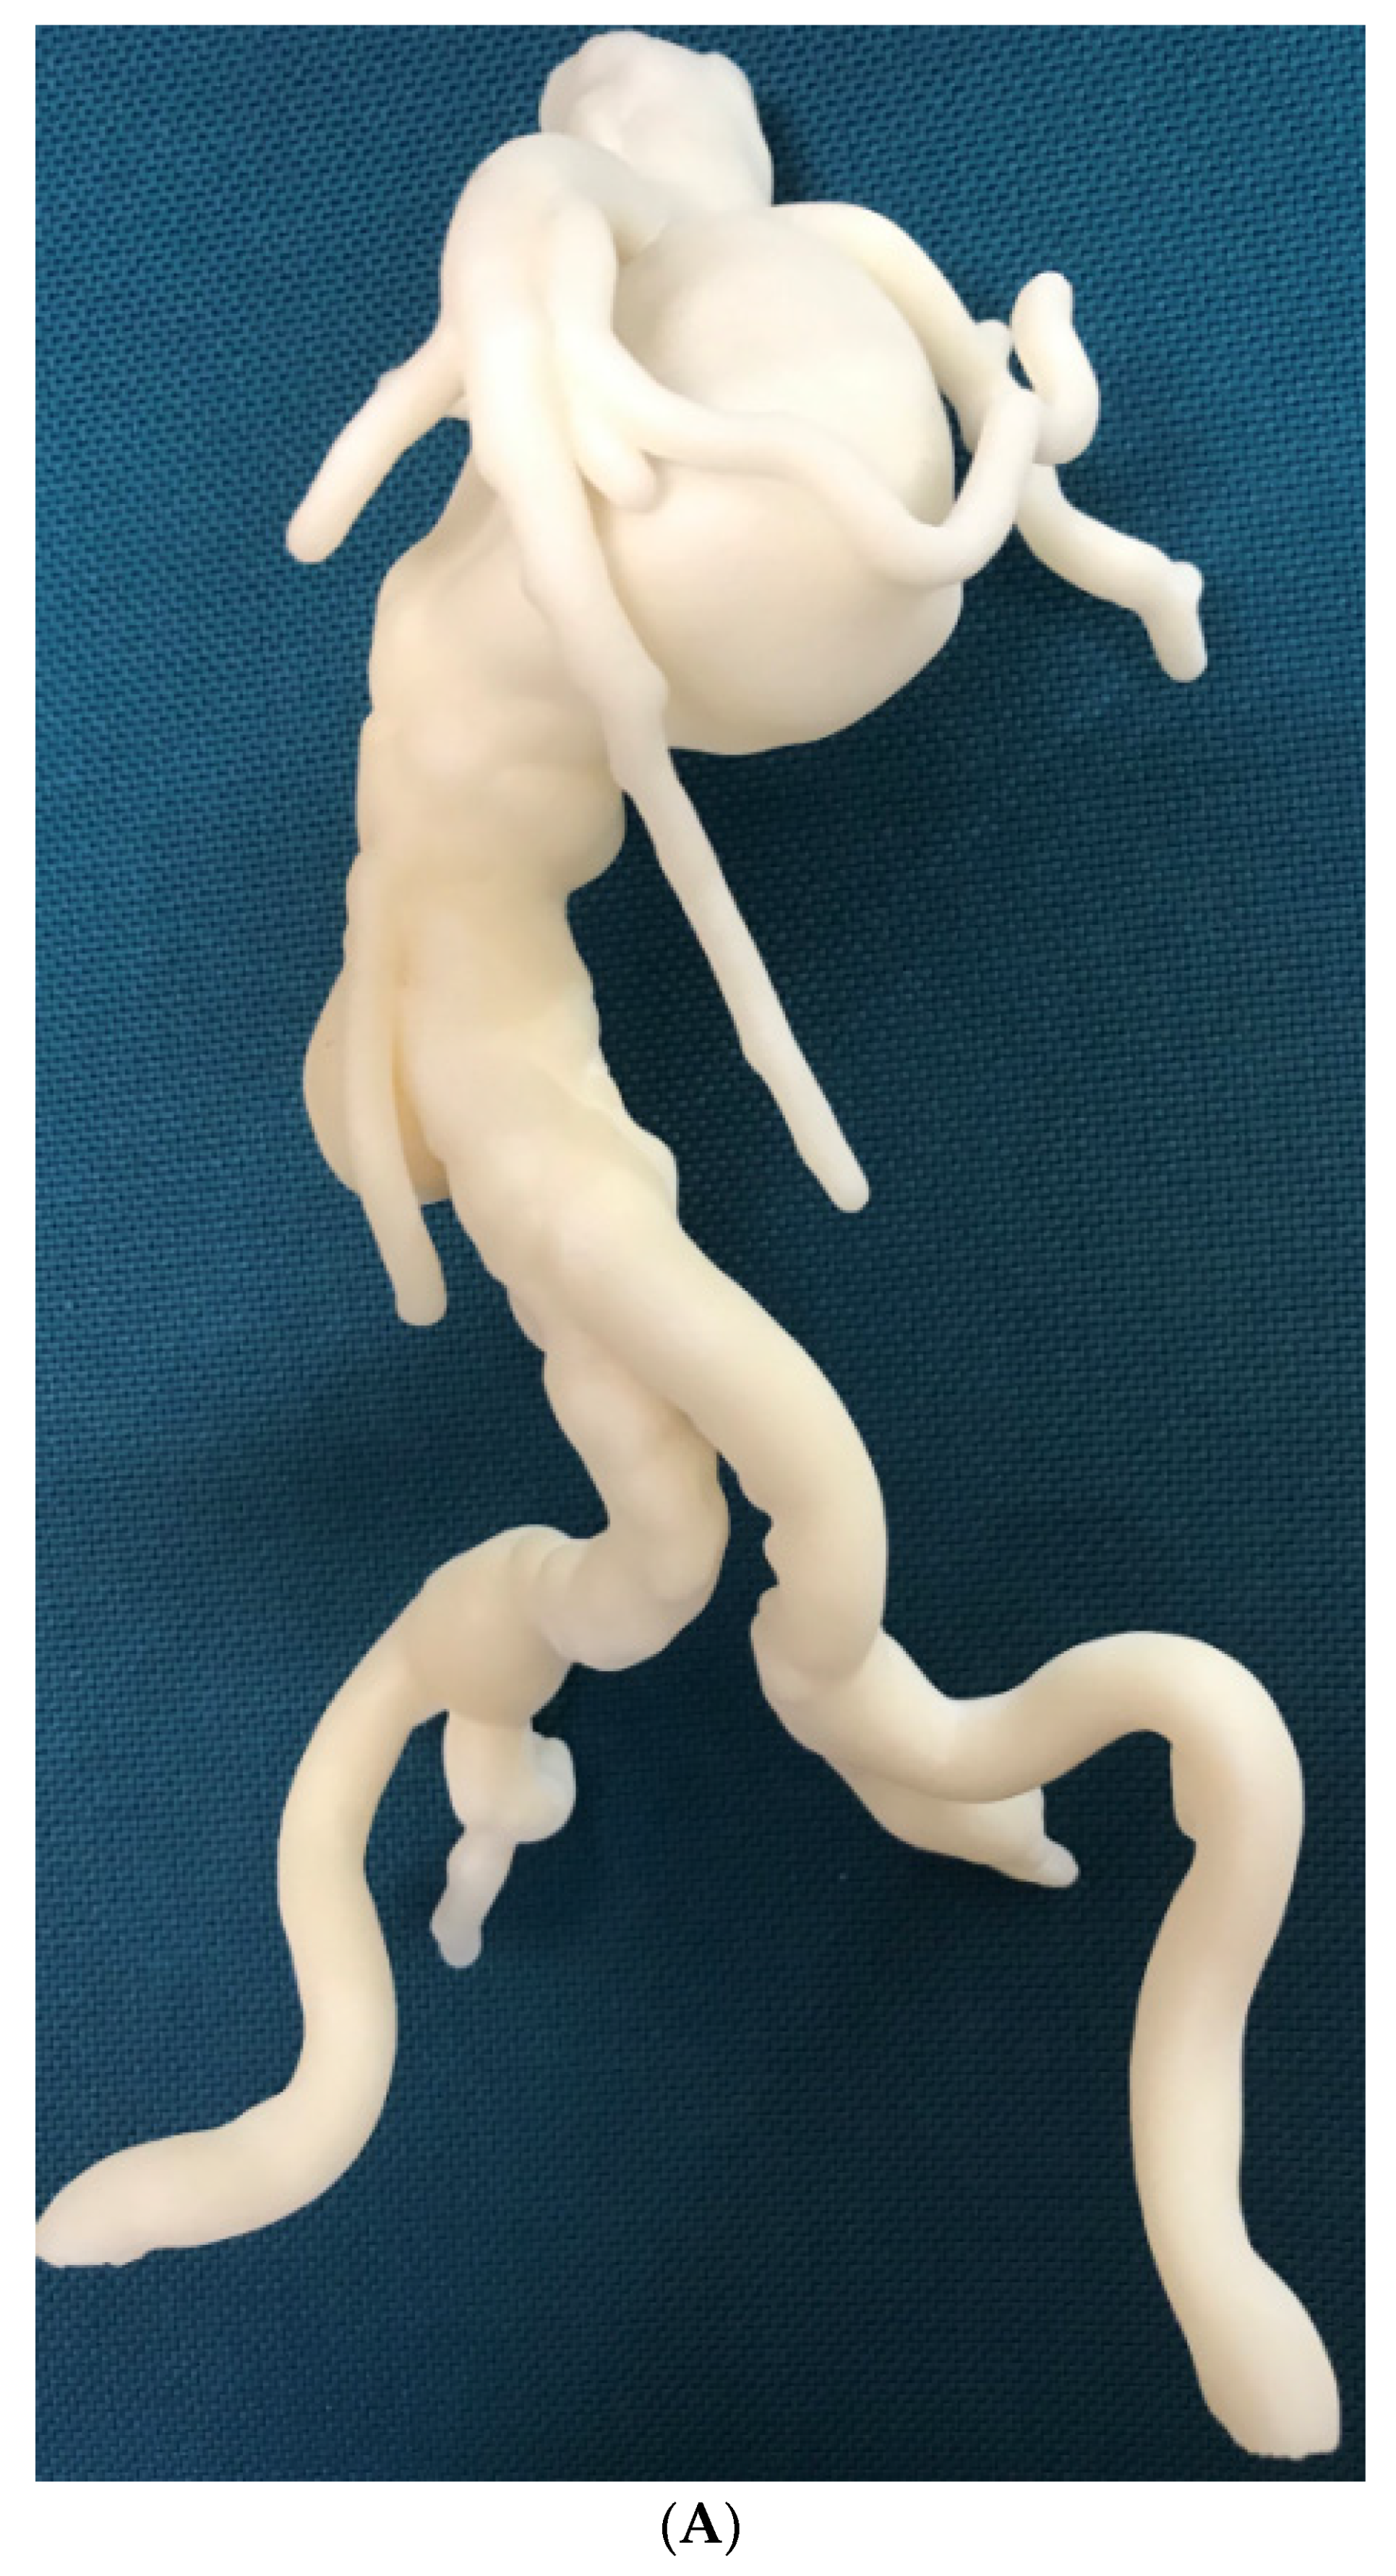

3.4. 3D Printing in Aortic Aneurysm and Aortic Dissection

- Ho, D.; Squelch, A.; Sun, Z. Modelling of aortic aneurysm and aortic dissection through 3D printing. J. Med. Radiat. Sci. 2017, 64, 10–17. [Google Scholar] [CrossRef] [PubMed]

- Sun, Z.; Squelch, A. Patient-specific 3D printed models of aortic aneurysm and aortic dissection. J. Med. Imaging Health Inf. 2017, 7, 886–889. [Google Scholar] [CrossRef]